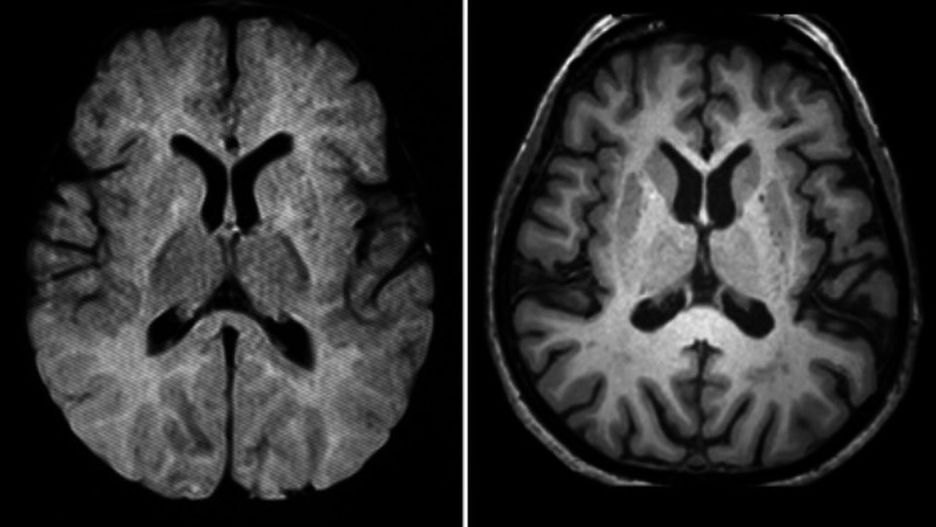

Se trata de un hito histórico. Un grupo de investigadores británicos ha conseguido frenar por primera vez la enfermedad de Huntington, una grave trastorno neurológico y degenerativo que produce el desgaste de algunas células del cerebro y provoca movimientos incontrolados, la pérdida de facultades intelectuales y perturbación emocional, gracias a un nuevo fármaco en fase experimental.

El Ionis-HTTRx consiguió interceptar la molécula mensajera que se encarga de poner en marcha la huntingtina, la proteína tóxica que activa el mecanismo por el que se desarrolla la enfermedad. Tras el tratamiento, la concentración de la proteína dañina en el fluido de la médula espinal disminuyó significativamente y en proporción con la intensidad de la dosis.

El hallazgo resulta especialmente significativo porque, tal y como apunta el diario británico, los resultados podrían adaptarse a otros trastornos cerebrales incurables como el Alzheimer o el Parkinson. "Si me hubiesen preguntado hace cinco años si esto podría funcionar, habría dicho que no. El hecho de que haya resultado es realmente notable", asegura el investigador John Hardy.